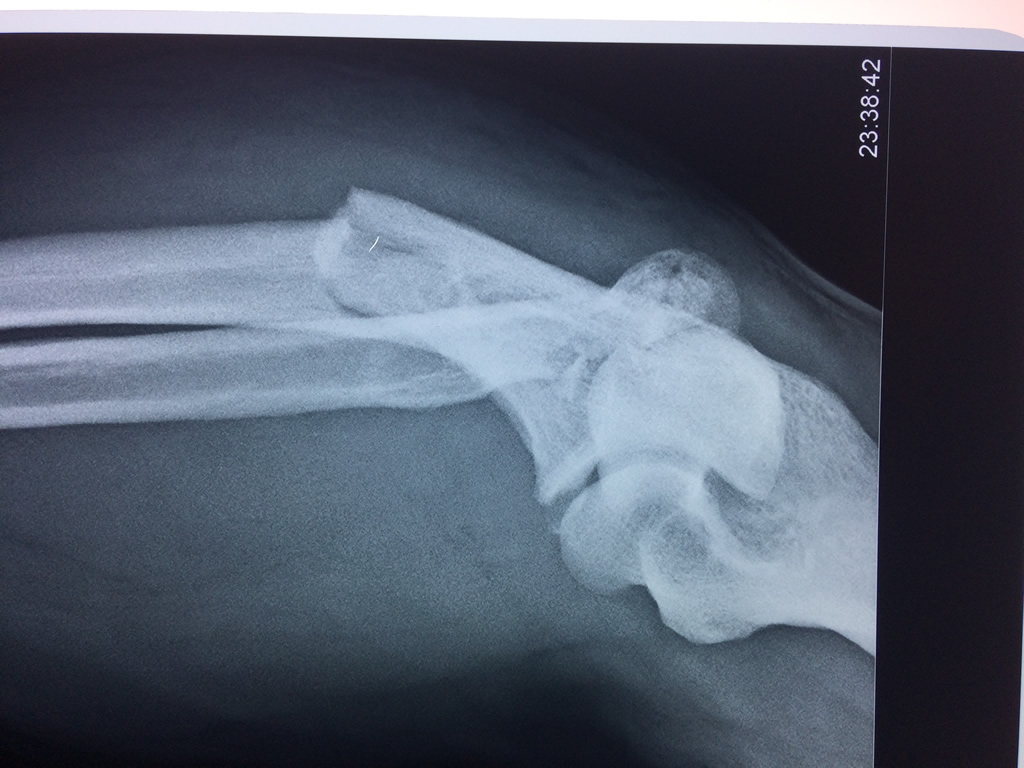

En anatomía humana, la articulación del codo es la que une el brazo con el antebrazo, conectando la parte distal del hueso húmero con los extremos proximales de los huesos cúbito y radio.

La articulación principal que constituye el codo se denomina humero radio-cubital y puede dividirse en dos partes bien diferenciadas, la articulación humero-radial y la humero-cubital.

Por otra parte el cúbito y el radio forman también una articulación entre si en las proximidades del codo, la cual se denomina articulación radio-cubital proximal.